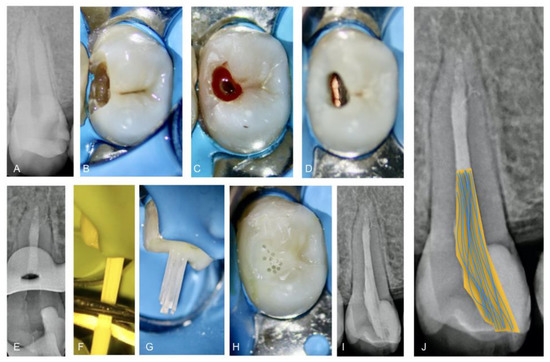

2.2. Restorative Procedures: Post Placement and Composite Restoration